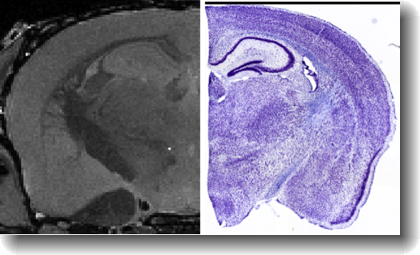

Validation with a in situ MRI scan and the histological digital scan is shown next:

- Validated to MRM Imaged Brains